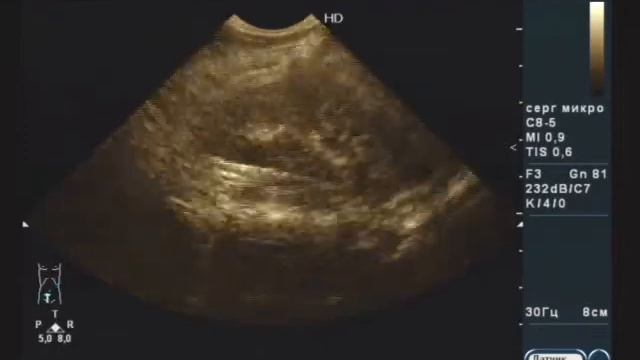

синус повышенной эхогенности

Почечный синус повышенной эхогенности 112 фотографий